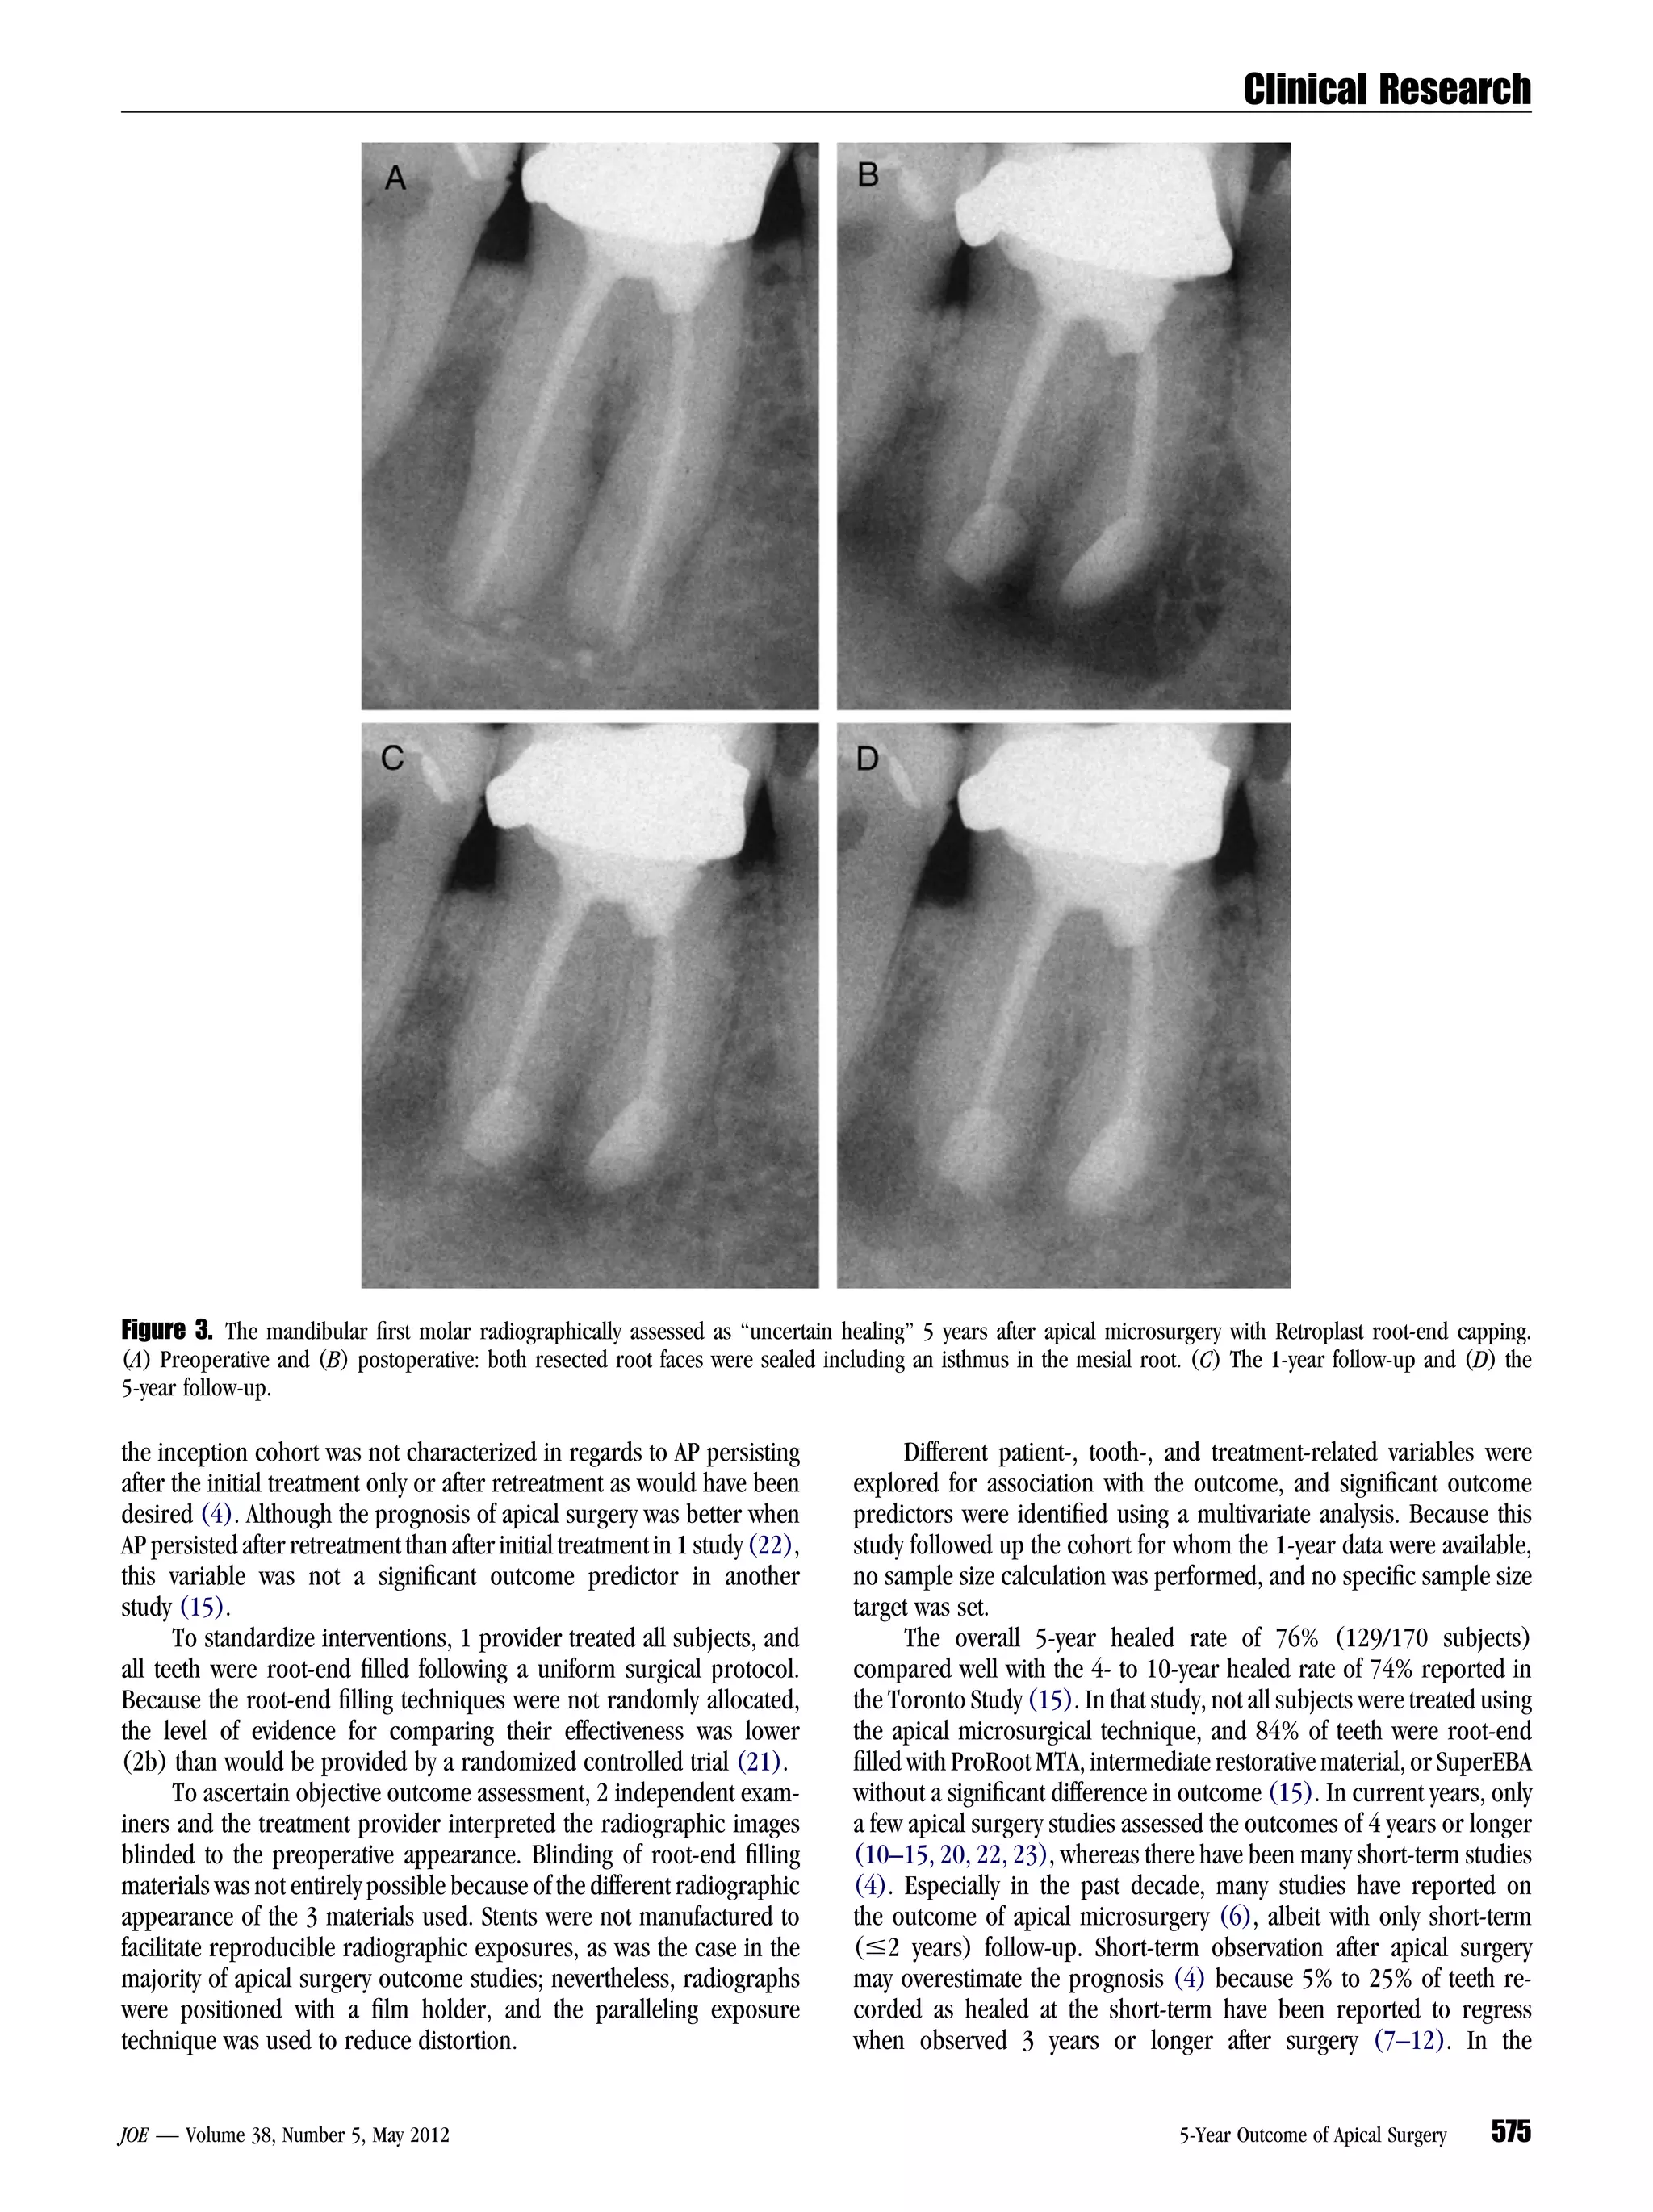

Figure 3. The mandibular first molar radiographically assessed as ‘‘uncertain healing’’ 5 years after apical microsurgery with Retroplast root-end capping.

(A) Preoperative and (B) postoperative: both resected root faces were sealed including an isthmus in the mesial root. (C) The 1-year follow-up and (D) the

5-year follow-up.